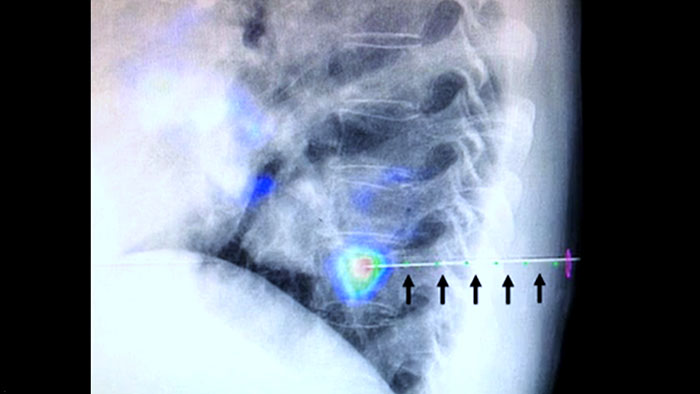

XperGuide proporciona una guía de imagen en vivo de alta precisión de cada aguja a una posición determinada mediante la superposición de trayectorias preplanificadas con imágenes fluoroscópicas.3